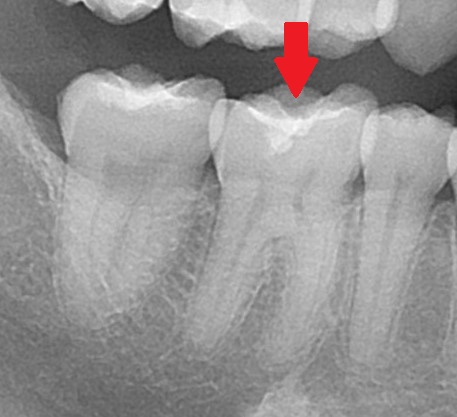

実際のレジンの中の虫歯を見てみましょう。

ここまでの話を理解している方は一目瞭然だと思いますが、赤い矢印の歯に虫歯があります。

また、レジンは銀歯と違いレントゲン写真で、真っ白に写りません。

そのため、今回の虫歯も分かりやすいと思います。

うっすら詰めてあるのが分かりますので、スケルトンじゃないですが、レジンの下に黒い虫歯があるのがわかります。

周囲の他の歯には真っ白な銀歯が入っていますね。

お口の中はというと、

矢印の歯がレジンで詰めてあります。白い色の材料なので分かりにくいでしょうか。

こちらの詰め物の中に虫歯があります。

レジンはレントゲン写真でうっすらと写るために虫歯が確認できます。

また「セラミック」も同じようにうっすらと写るので、詰め物の下で虫歯になっている場合分かりやすい材料であると言えます。